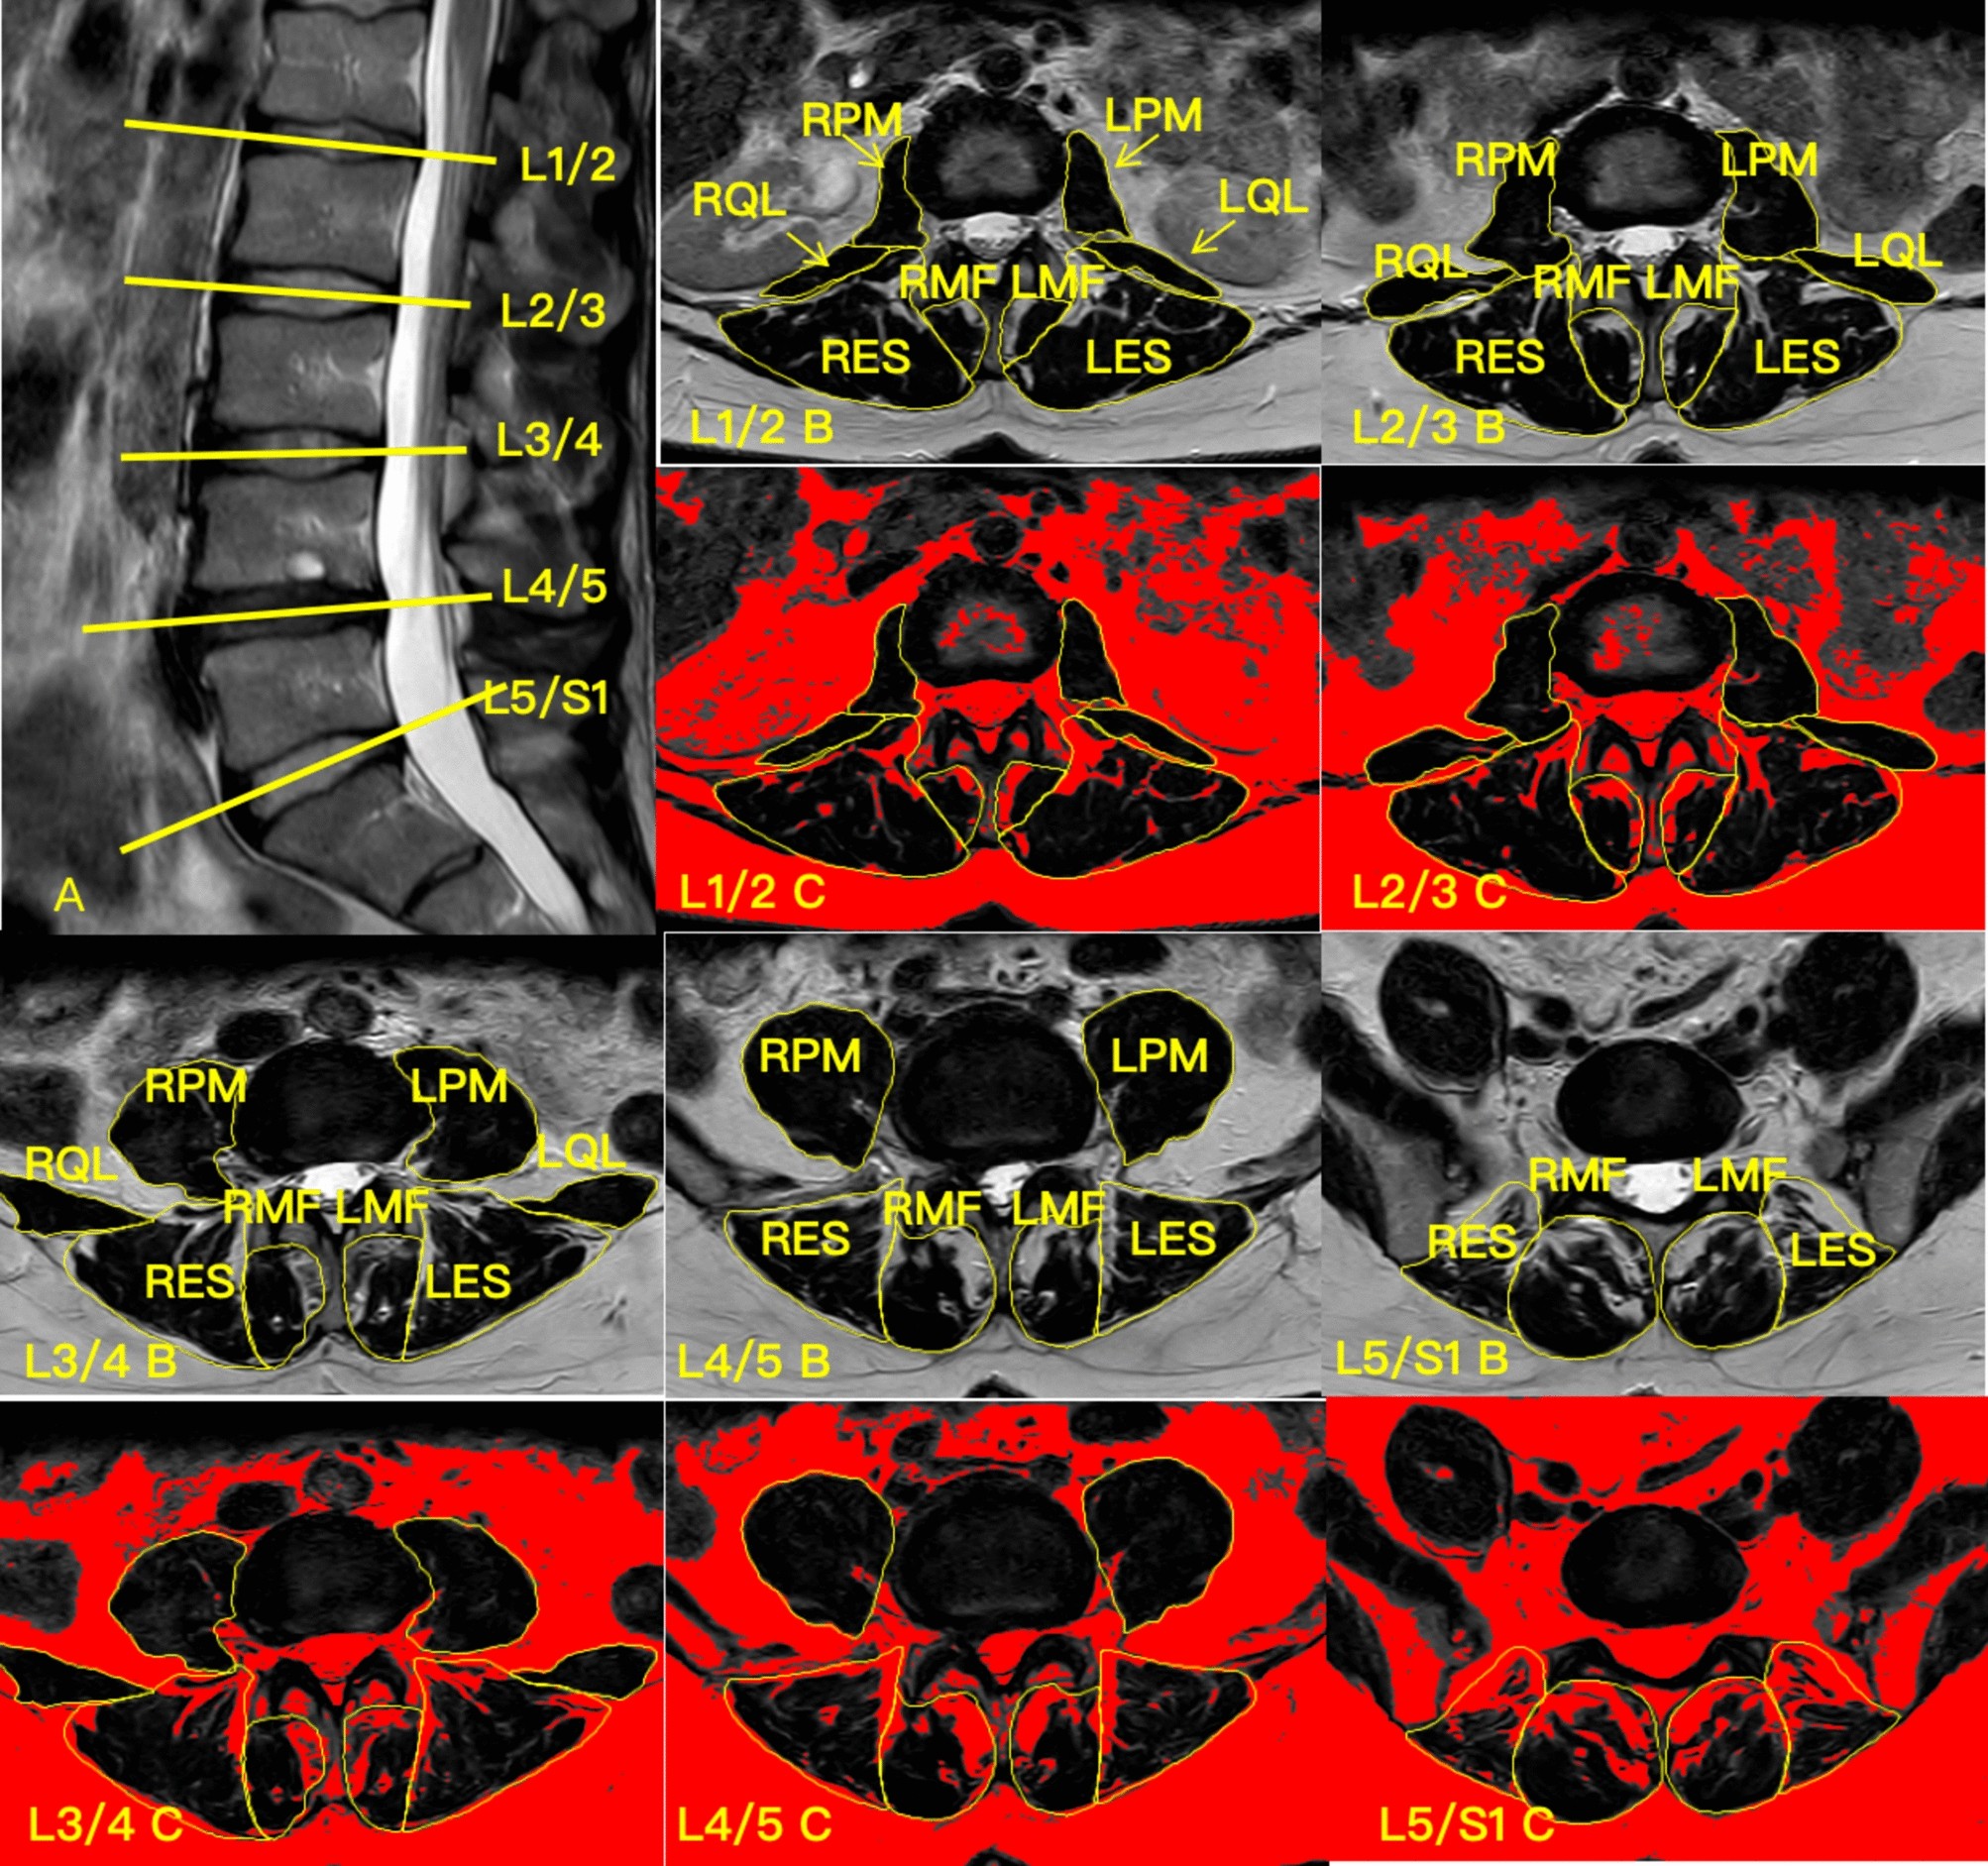

Fig. 1

MRI of a subject’s lumbar spine and target muscle measurements. (A) Sagittal view of the lumbar spine, with the yellow line indicating the location of the measured cross-sectional MRI; (B) Cross-sectional area of the psoas major (PM), quadratus lumborum (QL), multifidus (MF), and erector spinae (ES) at the L1/2 segment; (C) Functional cross-sectional area of the PM, QL, MF and ES at the L1/2 segment. LPM left psoas major, LQL left quadratus lumborum, LMF left multifidus, LES left erector spinae, RPM right psoas major, RQL right quadratus lumborum, RMF right multifidus, RES right erector spinae.